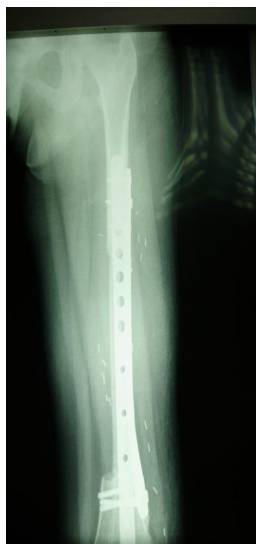

Ameliyat Esnası: Rezeksiyon sonrası vasülerize fibula uygulanımı ve titanyum plak ile fiksasyon görülmekte

Ameliyat Sonrası: Röntgende rezeksiyon sonrası vasülerize fibula uygulanımı ve çift plak ile fiksasyon görülmekte